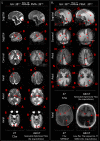

Findings: Between September 23, 2021 and October 25, 2022, 102 paired scans were acquired in 87 infants; 1.17 paired scans per infant. Median age 9 days, median postmenstrual age 40+2 weeks (range: 31+3-53+4). Infants had a range of intensive care requirements. No adverse events observed. Optimised ULF sequences can visualise key neuroanatomy and brain abnormalities. In finalised neonatal sequences: T2w imaging distinguished grey and white matter (7/7 infants), ventricles (7/7), pituitary tissue (5/7), corpus callosum (7/7) and optic nerves (7/7). Signal congruence was seen within the posterior limb of the internal capsule in 10/11 infants on finalised T1w scans. In addition, brain abnormalities visualised on ULF optimised sequences have similar MR signal patterns to 3T imaging, including injury secondary to infarction (6/6 infants on T2w scans), hypoxia-ischaemia (abnormal signal in basal ganglia, thalami and white matter 2/2 infants on T2w scans, cortical highlighting 1/1 infant on T1w scan), and congenital malformations: polymicrogyria 3/3, absent corpus callosum 2/2, and vermian hypoplasia 3/3 infants on T2w scans. Sequences are susceptible to motion corruption, noise, and ULF artefact. Non-identified pathologies were small or subtle.